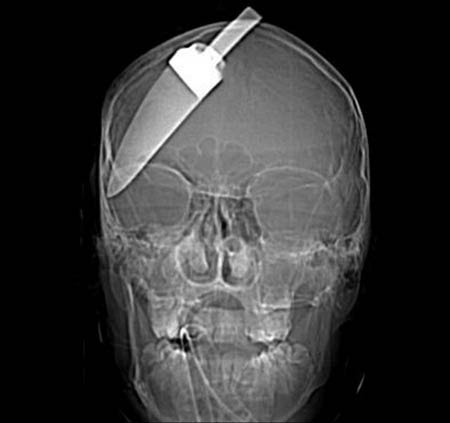

La scioccante radiografia del paziente, diffusa martedì da Scotland Yard, mostra quanto la lama, di circa 13 centimetri, sia entrata in profondità nel suo cranio, appena sopra l'occhio fermandosi sopra l'orecchio, senza però ledere parti vitali o il cervello. Il feroce attacco risale a una decina di mesi fa - il giovane è sopravvissuto senza gravi conseguenze e nel frattempo è ritornato di nuovo a scuola. Tuttavia, hanno riferito i medici, se qualcuno dei suoi amici o qualche soccorritore avesse tentato di estrarlo, sarebbe stata una morte certa. Uno degli assalitori, di appena 17 anni, è stato arrestato poco dopo il crimine. Altri due ragazzi sono tuttora latitanti.

The shocking snapshot of the patient, circulated Tuesday by Scotland Yard, shows how the blade, approximately 13 cm, has entered deeply into his skull, just above the eye, stopping above the ear, but did not affect vital parts and brains. The ferocious attack goes back about ten months ago - the young man survived without serious consequences and in the meantime is returned back to school. However, doctors have reported, though some of his friends or some rescuer had tried to extract it, would have been a certain death. One of the assailants, just 17 years, was arrested shortly after the crime. Two other boys are still fugitives.